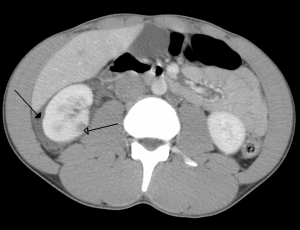

Right kidney contusion (open arrow) and blood surrounding the kidney (closed arrow).